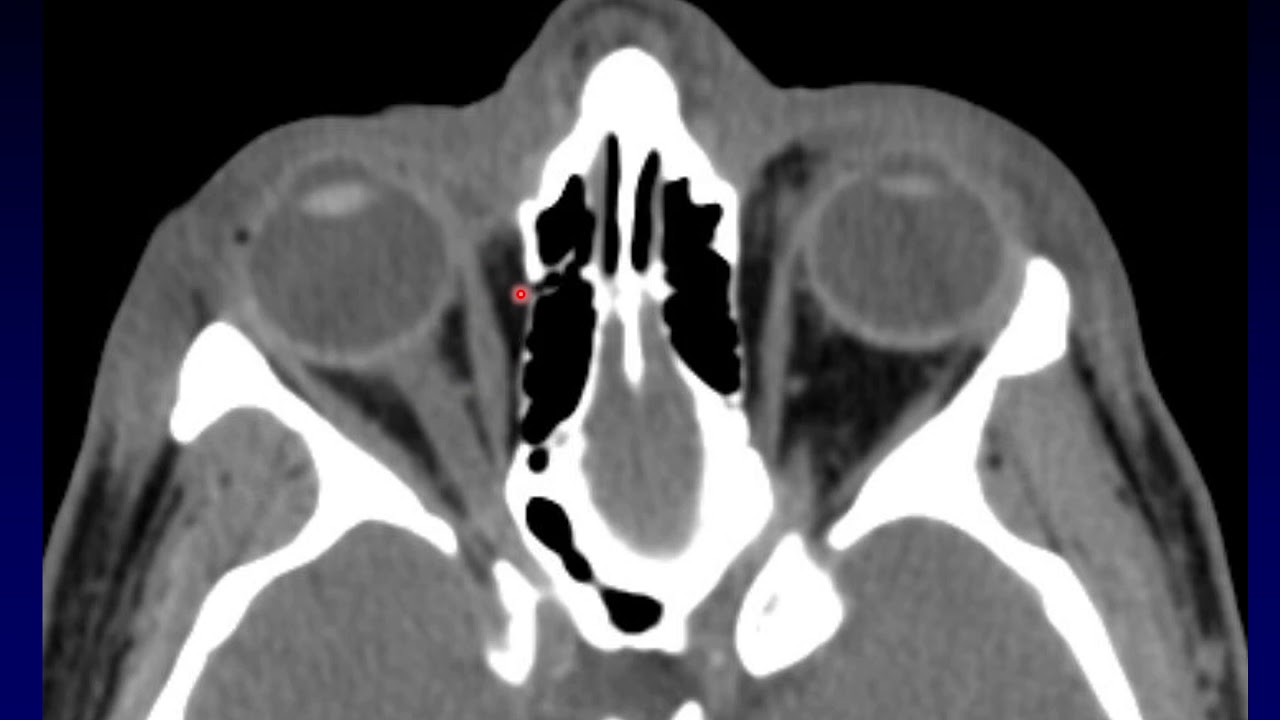

Imaging of the Eye and Orbit, Part 4

Автор: Barton Branstetter (ENT Imaging Lectures)

Описание: Part 4 of the Orbit lecture